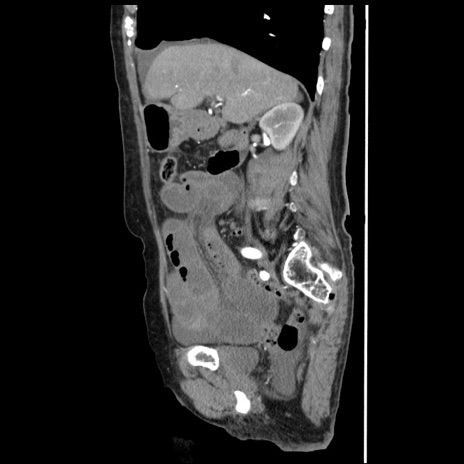

冠状断像

【症例】80歳代女性

【主訴】腹痛

【現病歴】8時間前から腹痛あり来院。

【既往歴】糖尿病、脂質異常症、子宮体癌にて子宮全摘術

【身体所見】意識清明・会話良好だが腹痛で苦悶様、全腹部にわたって反跳痛と圧痛あり

【データ】WBC 13600、CRP 0.14、LDH 224、CK 90